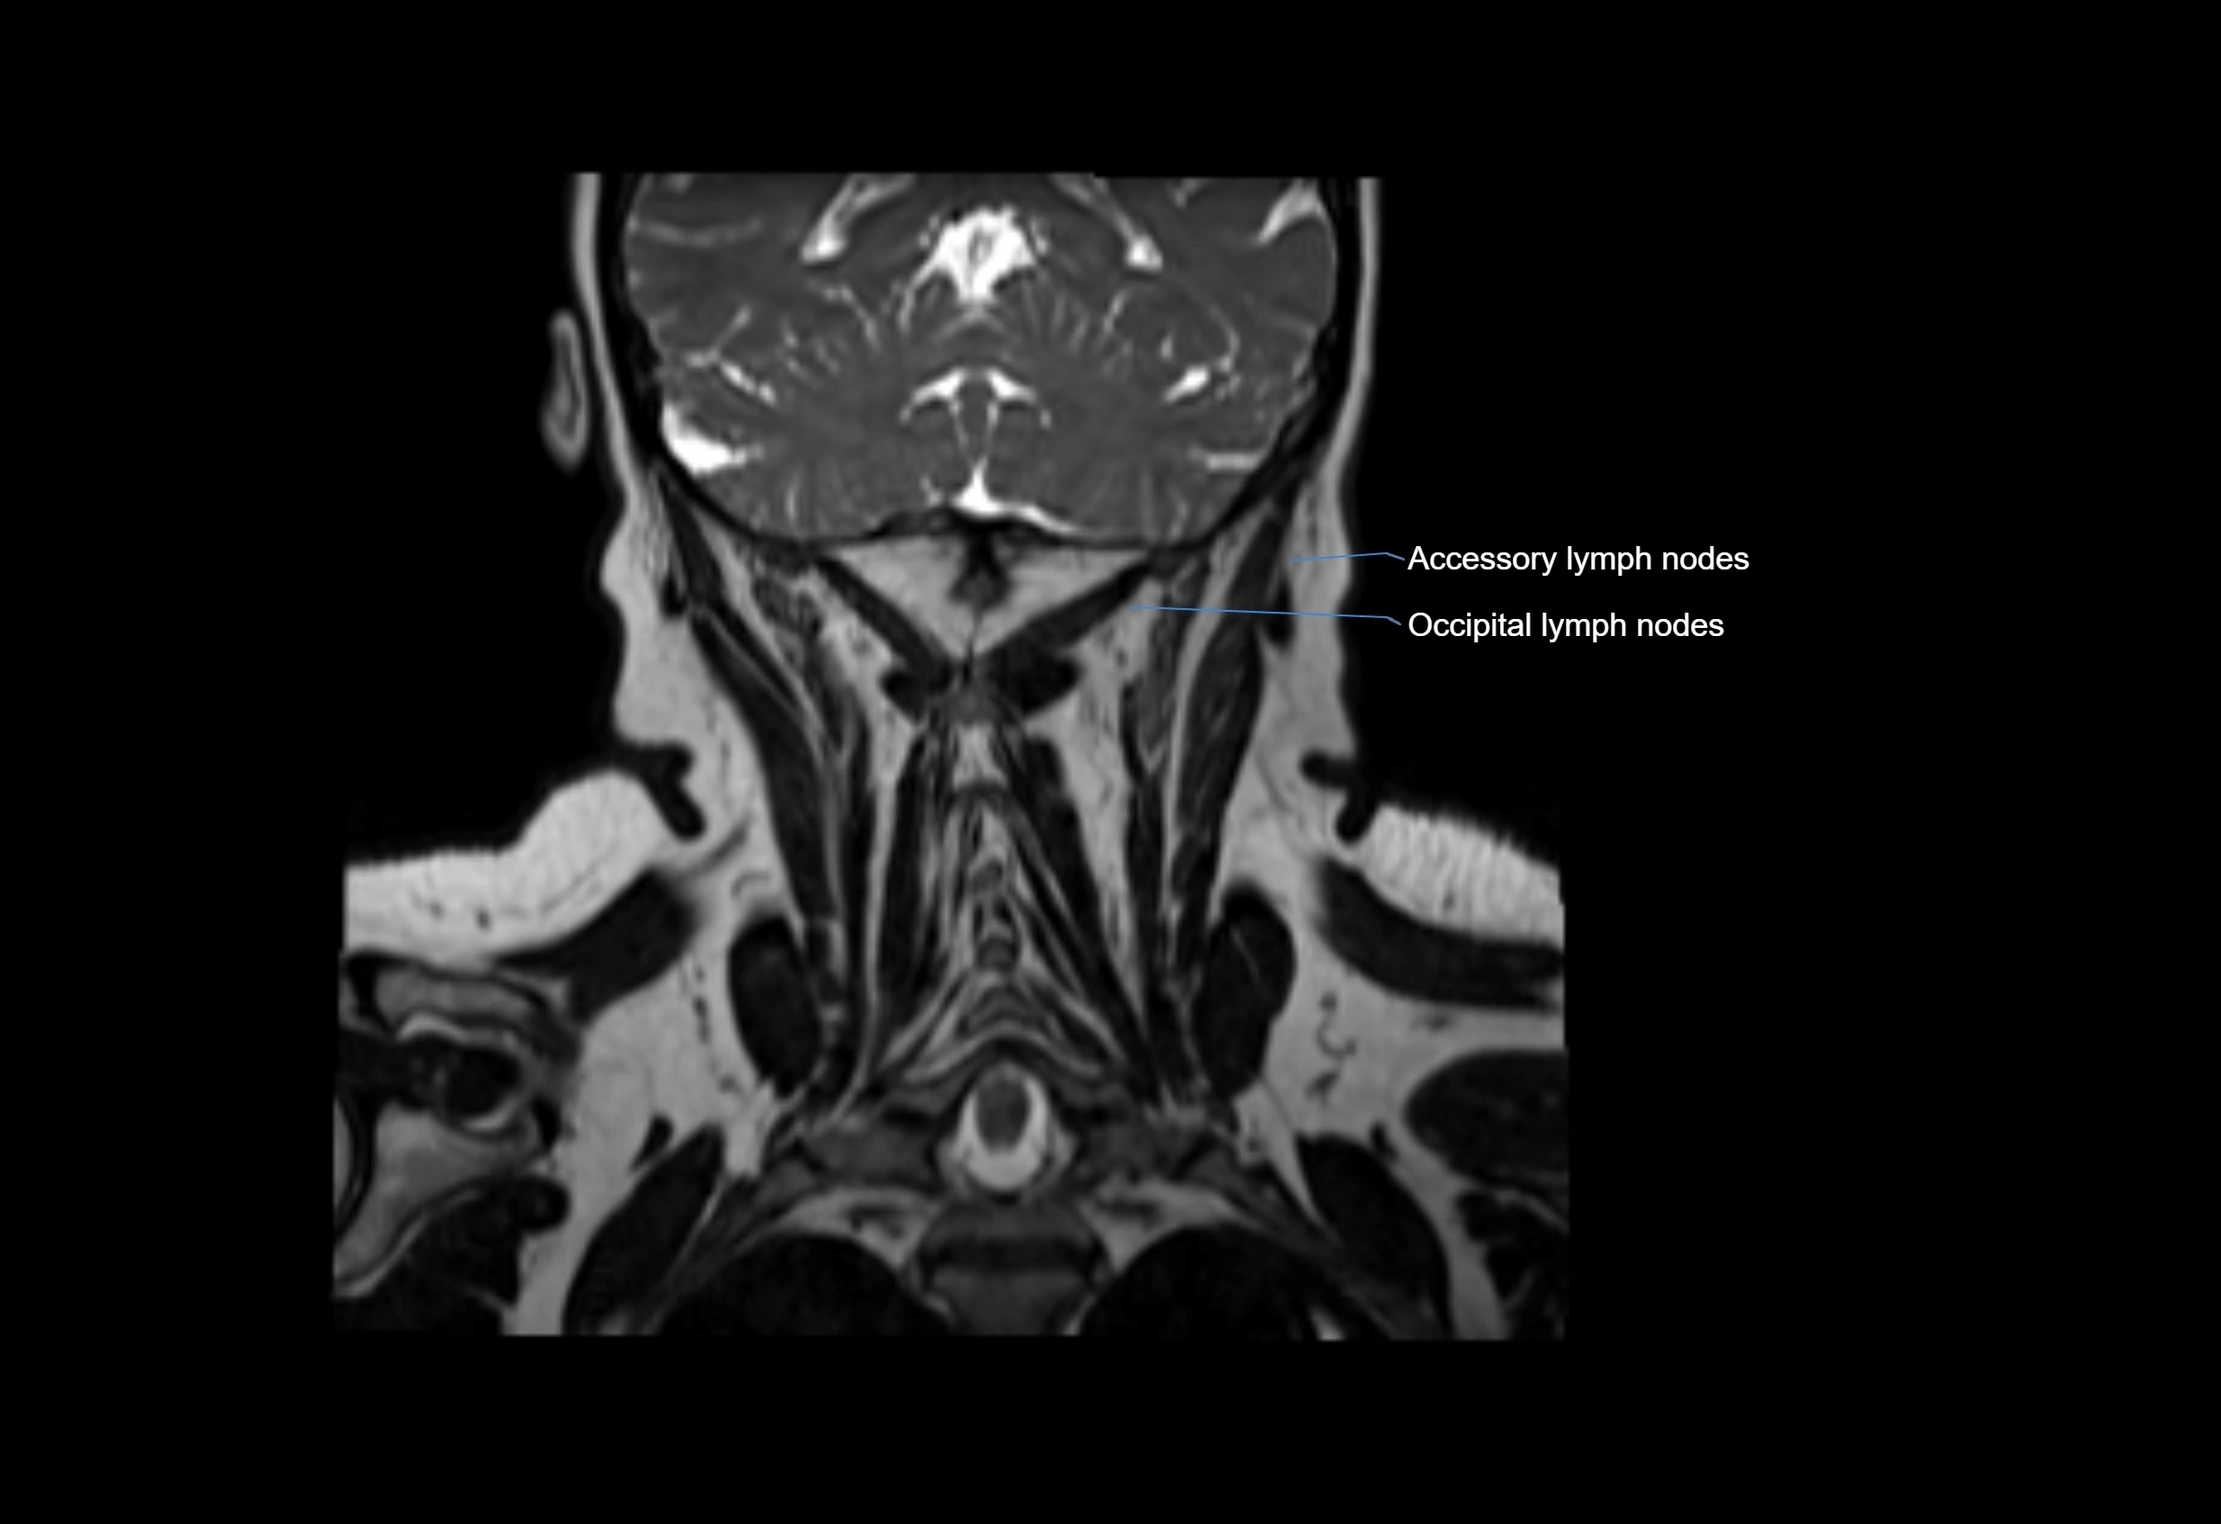

Accessory lymph nodes are small, secondary lymph nodes located along the main facial and cervical lymphatic chains, often adjacent to primary lymph nodes, such as preauricular, submandibular, or occipital nodes. They are typically less than 5 mm in diameter, embedded within subcutaneous fat or connective tissue, and may be variable in number and location. These nodes provide additional filtration and immune surveillance for lymph collected from the face, scalp, and neck regions. Accessory lymph nodes are usually non-palpable in healthy individuals but may enlarge in response to infection, inflammation, or metastasis, making them clinically significant.

Location

• Found along primary lymph node chains, including preauricular, submandibular, parotid, and occipital regions

• Embedded in subcutaneous fat or superficial fascia, often lateral or posterior to primary nodes

• Variable in number; may occur unilaterally or bilaterally, depending on individual anatomy

MRI Appearance

T1-weighted images:

• Normal accessory nodes appear as small, oval hypointense to intermediate signal structures within subcutaneous fat

• Surrounded by hyperintense fat, enhancing contrast for visualization

• Pathological nodes may appear enlarged or rounded, sometimes with cortical thickening

T2-weighted images:

• Nodes show intermediate signal, with surrounding fat bright

• Useful for detecting edema, inflammation, or infiltration

• Fatty hilum may appear slightly hyperintense relative to cortex

MRI images

image